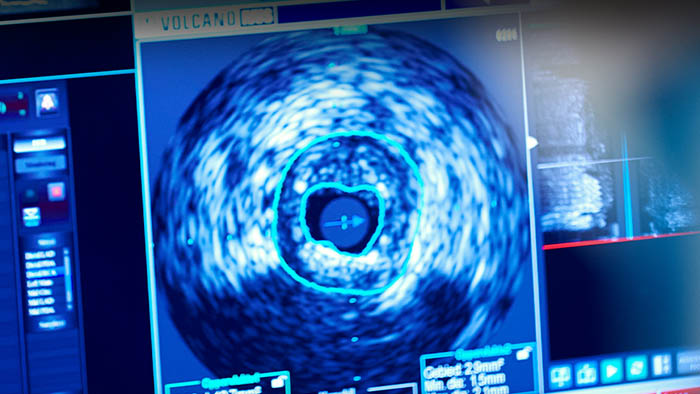

• Échographie intravasculaire (IVUS)

L’échographie intravasculaire (IVUS) est une technologie d’imagerie par cathéter permettant aux médecins de visualiser les vaisseaux malades depuis l’intérieur de l’artère.